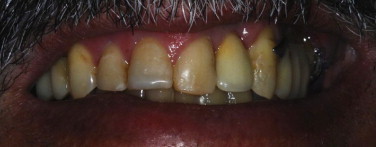

Fig. 10.

Frontal view of the clinical aspect after the case finalization.